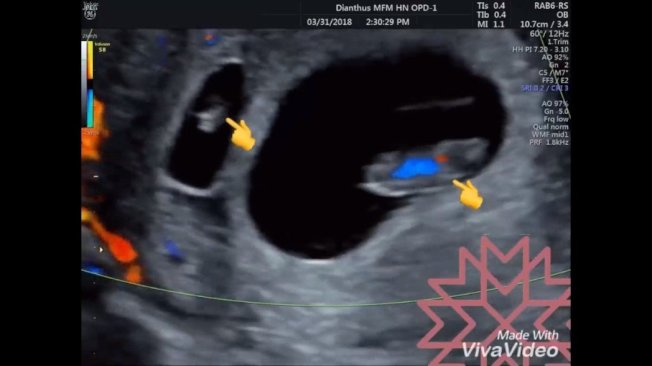

一位怀孕八周的妈妈产周,赫然发现旁边多一个六周的胎儿,让苏怡宁感到惊奇。图/撷取至苏怡宁医师爱碎念脸书粉丝页

苏怡宁脸书PO文说,一位妈咪怀孕八周来做产检,很惊奇的在原本该预期的八周胎儿旁边,不预期的出现了另一个六周的胚胎,头臀围差两公分正好就是两周的差距,他也很确定两周前确定只看到一个胚胎,所以这是两个分别在两周间先后着床的双胞胎。

他表示,当下揉揉眼睛、深呼吸再看一次,心跳真的就在那儿,理论上几乎不太可能发生间隔两周各排一次卵的事情,在生理期荷尔蒙调控的机转上,真的很难发生但就是发生了!他难得的记录一下有关生命奇妙的一刻。